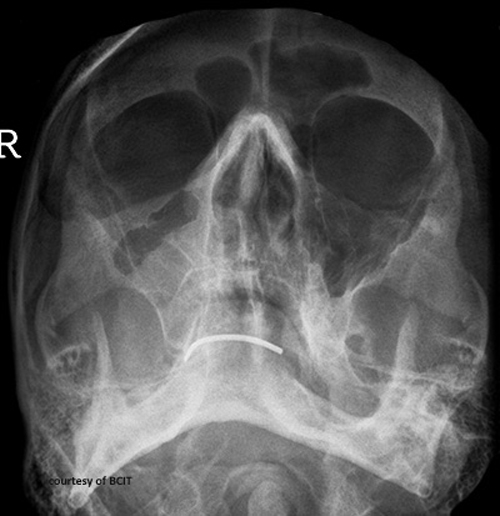

This treatment is required for the fracture seen here:

What is surgical plating (depressed fracture of zygomatic arch)